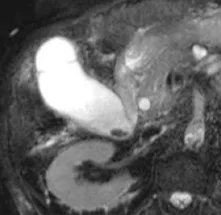

Figure 18. Mise en évidence d’une formation polypoïde (A, têtes de flèche) dans la lumière du canal hépatique commun. Cette coupe de bili-IRM montre les rapports entre le pôle supérieur de la lésion et la convergence biliaire supérieure. On note par ailleurs un abouchement variant sur le canal hépatique gauche du canal sectoriel postérieur droit (flèche). L’hypersignal tissulaire en T2 de la lésion (B) et son rehaussement en T1 après injection de gadolinium (C) montrent qu’il s’agit d’une tumeur et non d’un simple calcul ou d’un conglomérat de sludge. L’analyse de la pièce de résection chirurgicale a retrouvé un adénome tubulo-villeux de 2,5 cm de grand axe, dégénéré sous la forme d’un adénocarcinome bien différencié de type biliaire